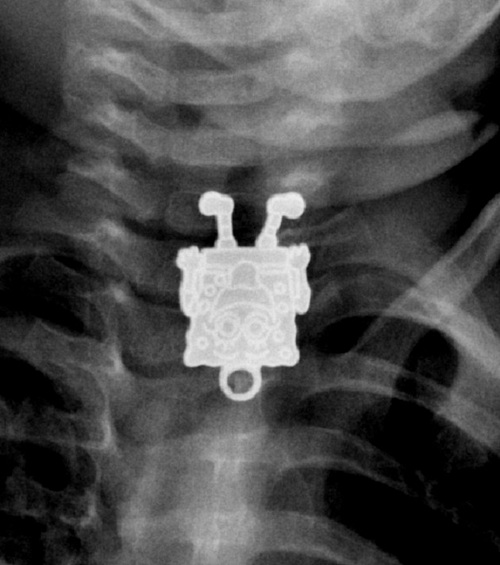

12 рентген‑фотографий, которые доказывают: идиотизм неистребим

Зачем и почему люди глотают разные странные вещи? Никто не знает точно, но медики утверждают, что таких “умников” гораздо больше, чем мы думаем.

Рентгенологи — люди с особо развитым чувством юмора. То, что они порой видят на снимках, у нормального человека вызовет настоящую истерику — а они только хмыкнут и отправят к хирургу. Что поделать, не расстраиваться же из-за каждого курьеза.